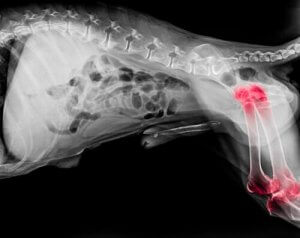

Arthritis in dogs

Experts believe that approximately one in five dogs is suffering from arthritis. While this joint condition can appear at any age, it’s more common in older dogs. Broadly speaking, arthritis is a degenerative disease which causes inflammation of both the elbow and shoulder joints.